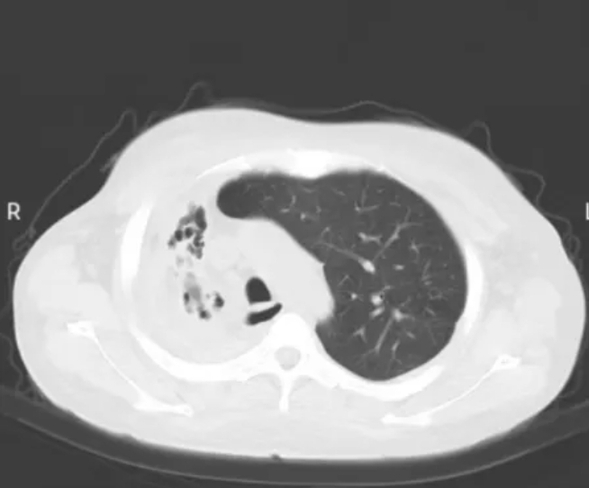

CT影像

为了明确肺部感染的病因,急需纤维支气管镜的辅助,纤维支气管镜是呼吸感染性疾病医生的好帮手。纤维支气管镜经口或鼻置入下呼吸道,进入气管或支气管以及更远端,医生通过显示屏成像或直接通过目镜,可以清晰的观察气管及支气管的病变。对于严重肺部感染的患者,可以行支气管肺泡灌洗,清除气道内的痰,栓塞,痰栓,以及纤维支气管镜灌洗过后可降低气道内的有害因子,增加气道清洁性,减少全身抗生素的使用。

我院感染科负责人张维彬与呼吸与危重症医学科一病区医生聂焱对患者进行了查体,结合资料,考虑在这种情况下,如果继续保守治疗,有可能导致患者病程时间长,感染迁延不愈。为了最大程度减少患者的痛苦,我院感染科医疗团队决定给予患者支气管镜下灌洗治疗术。在麻醉科和腔镜室等科室的协助下,我院感染科成功开展了首例纤维支气管镜检查、肺泡灌洗治疗技术,目前患者恢复疗效较好。